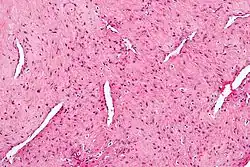

Micrograph of a nasopharyngeal angiofibroma. H&E stain.

Grossly, it is a firm mass that may be yellow, dark red, or even black. Histologically, it presents with several vascular spaces of varying sizes and wall thicknesses as well as fibrous or collagenous stroma with fibroblasts. Mast cells are common. Mitotic figures are usually not present.[5]